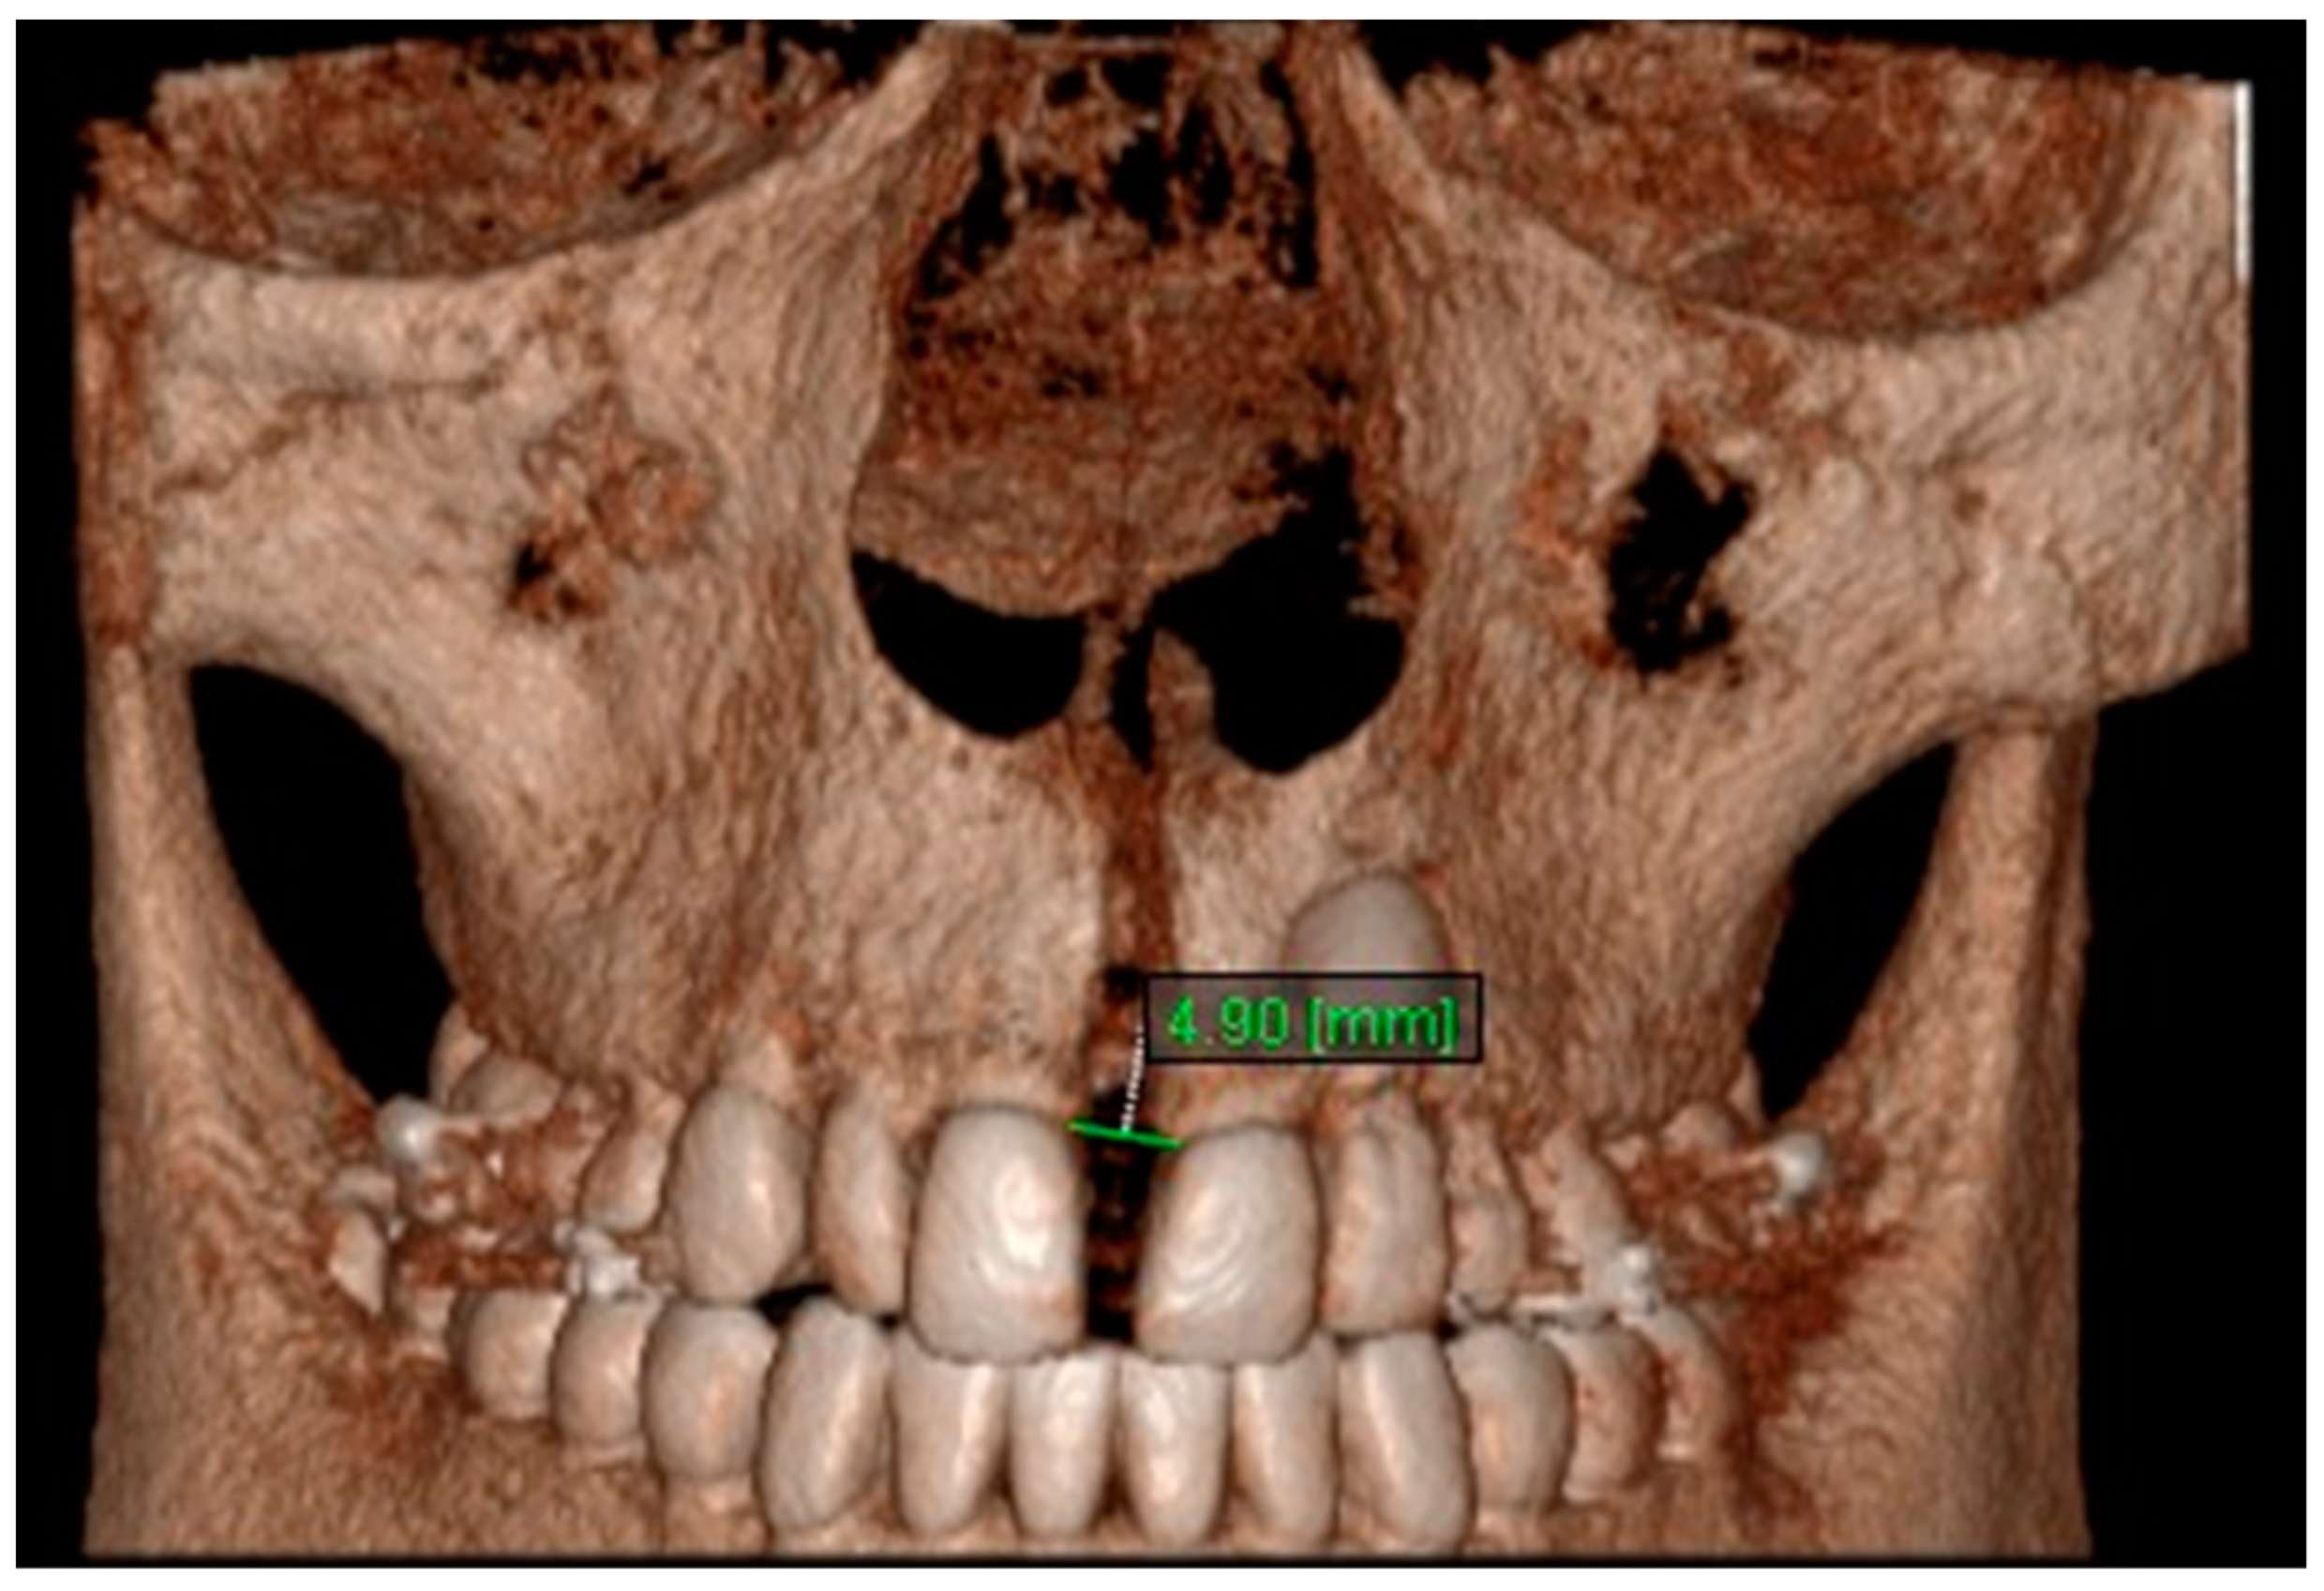

11. Aperture of Midpalatal Suture 11: The distance between the inner points of anterior median palatine suture, bilaterally in the inferior alveolar ridge of central incisors (Figure 13).

Figure 13.

Aperture of Midpalatal Suture 11.